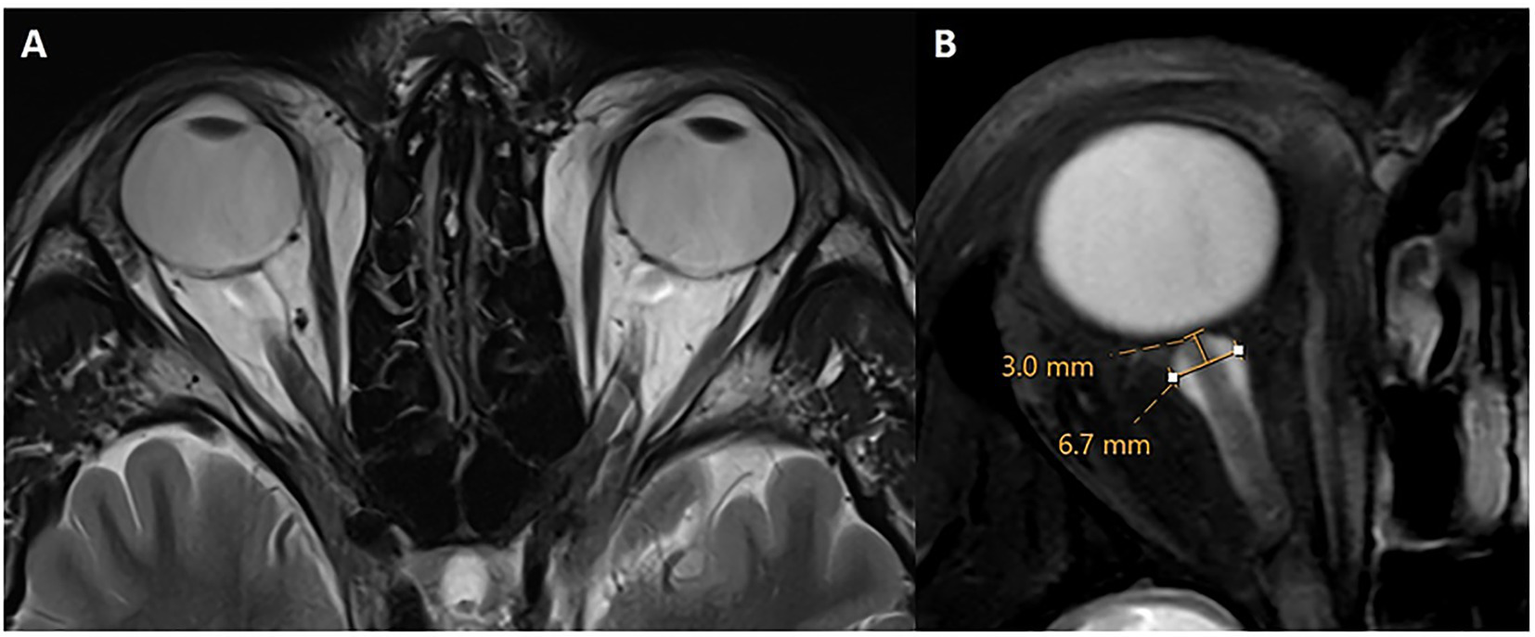

The intraorbital optic nerve (ON) and its arachnoid sheath were evaluated and measured on an axial 3D T2-weighted image with or without fat suppression, following established conventions (19, 28). ON tortuosity was defined as deviation of the intraorbital segment of the ON medially or laterally to an extent greater than or equal to the nerve width. Alternatively, failure to visualize a central segment of the ON, while the nerve is clearly seen both proximal and distal to that segment within the same imaging plane, was considered diagnostic of IIH. Optic nerve sheath (ONS) dilation was also assessed following established criteria (19, 28–35). Measurements were acquired at a consistent location along the distal intraorbital segment, 3 mm behind the posterior aspect of the globe (Figure 4). At this site, the ONS diameter was recorded, with a diameter of ≥5.60 mm considered indicative of IIH. While there is no single definitive threshold, values of >5.60 mm have been proposed (36). ONS tortuosity and dilation were combined into a single categorical variable (present/absent), reflecting their presence either independently or together.

Figure 4

Optic nerve sheath dilation and tortuosity. Axial T2w without (A) and with fat suppression (B) through the level of the optic nerve. There is bilateral tortuosity of the optic nerve and its sheath on both sides with a diameter of 6.7 mm in this case. Measurements of optic nerve sheath diameter were obtained 3 mm posterior to the optic globe.